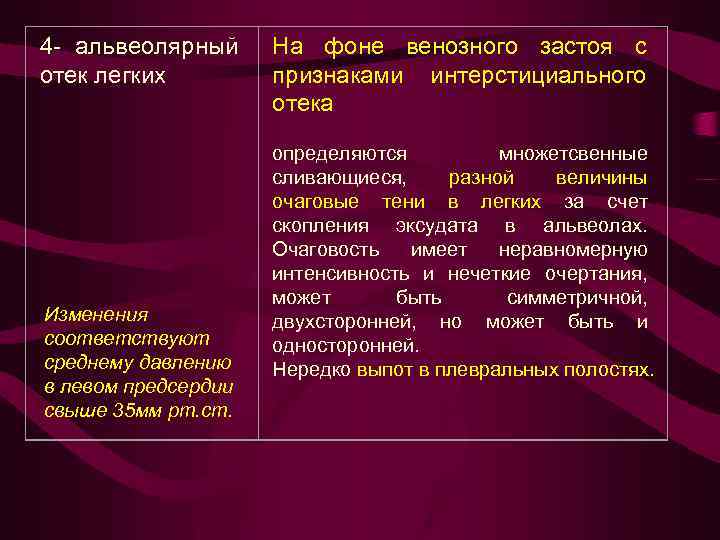

3 - интерстициальн ый отек легких Среднее давление в левом предсердии от 25 до 35 мм рт. ст. На фоне диффузного венозного застоя выявляются признаки нарушения лимфооттока из легких. Прозрачность легочных полей понижена. Легочный рисунок усилен, полиморфный, наблюдается ячеистая его деформация с нечеткостью контуров сосудов и бронхов. Выявляются линии Керли, Выпот в плевральную полость и междолевые щели, чаще справа.

3 - интерстициальн ый отек легких Среднее давление в левом предсердии от 25 до 35 мм рт. ст. На фоне диффузного венозного застоя выявляются признаки нарушения лимфооттока из легких. Прозрачность легочных полей понижена. Легочный рисунок усилен, полиморфный, наблюдается ячеистая его деформация с нечеткостью контуров сосудов и бронхов. Выявляются линии Керли, Выпот в плевральную полость и междолевые щели, чаще справа.